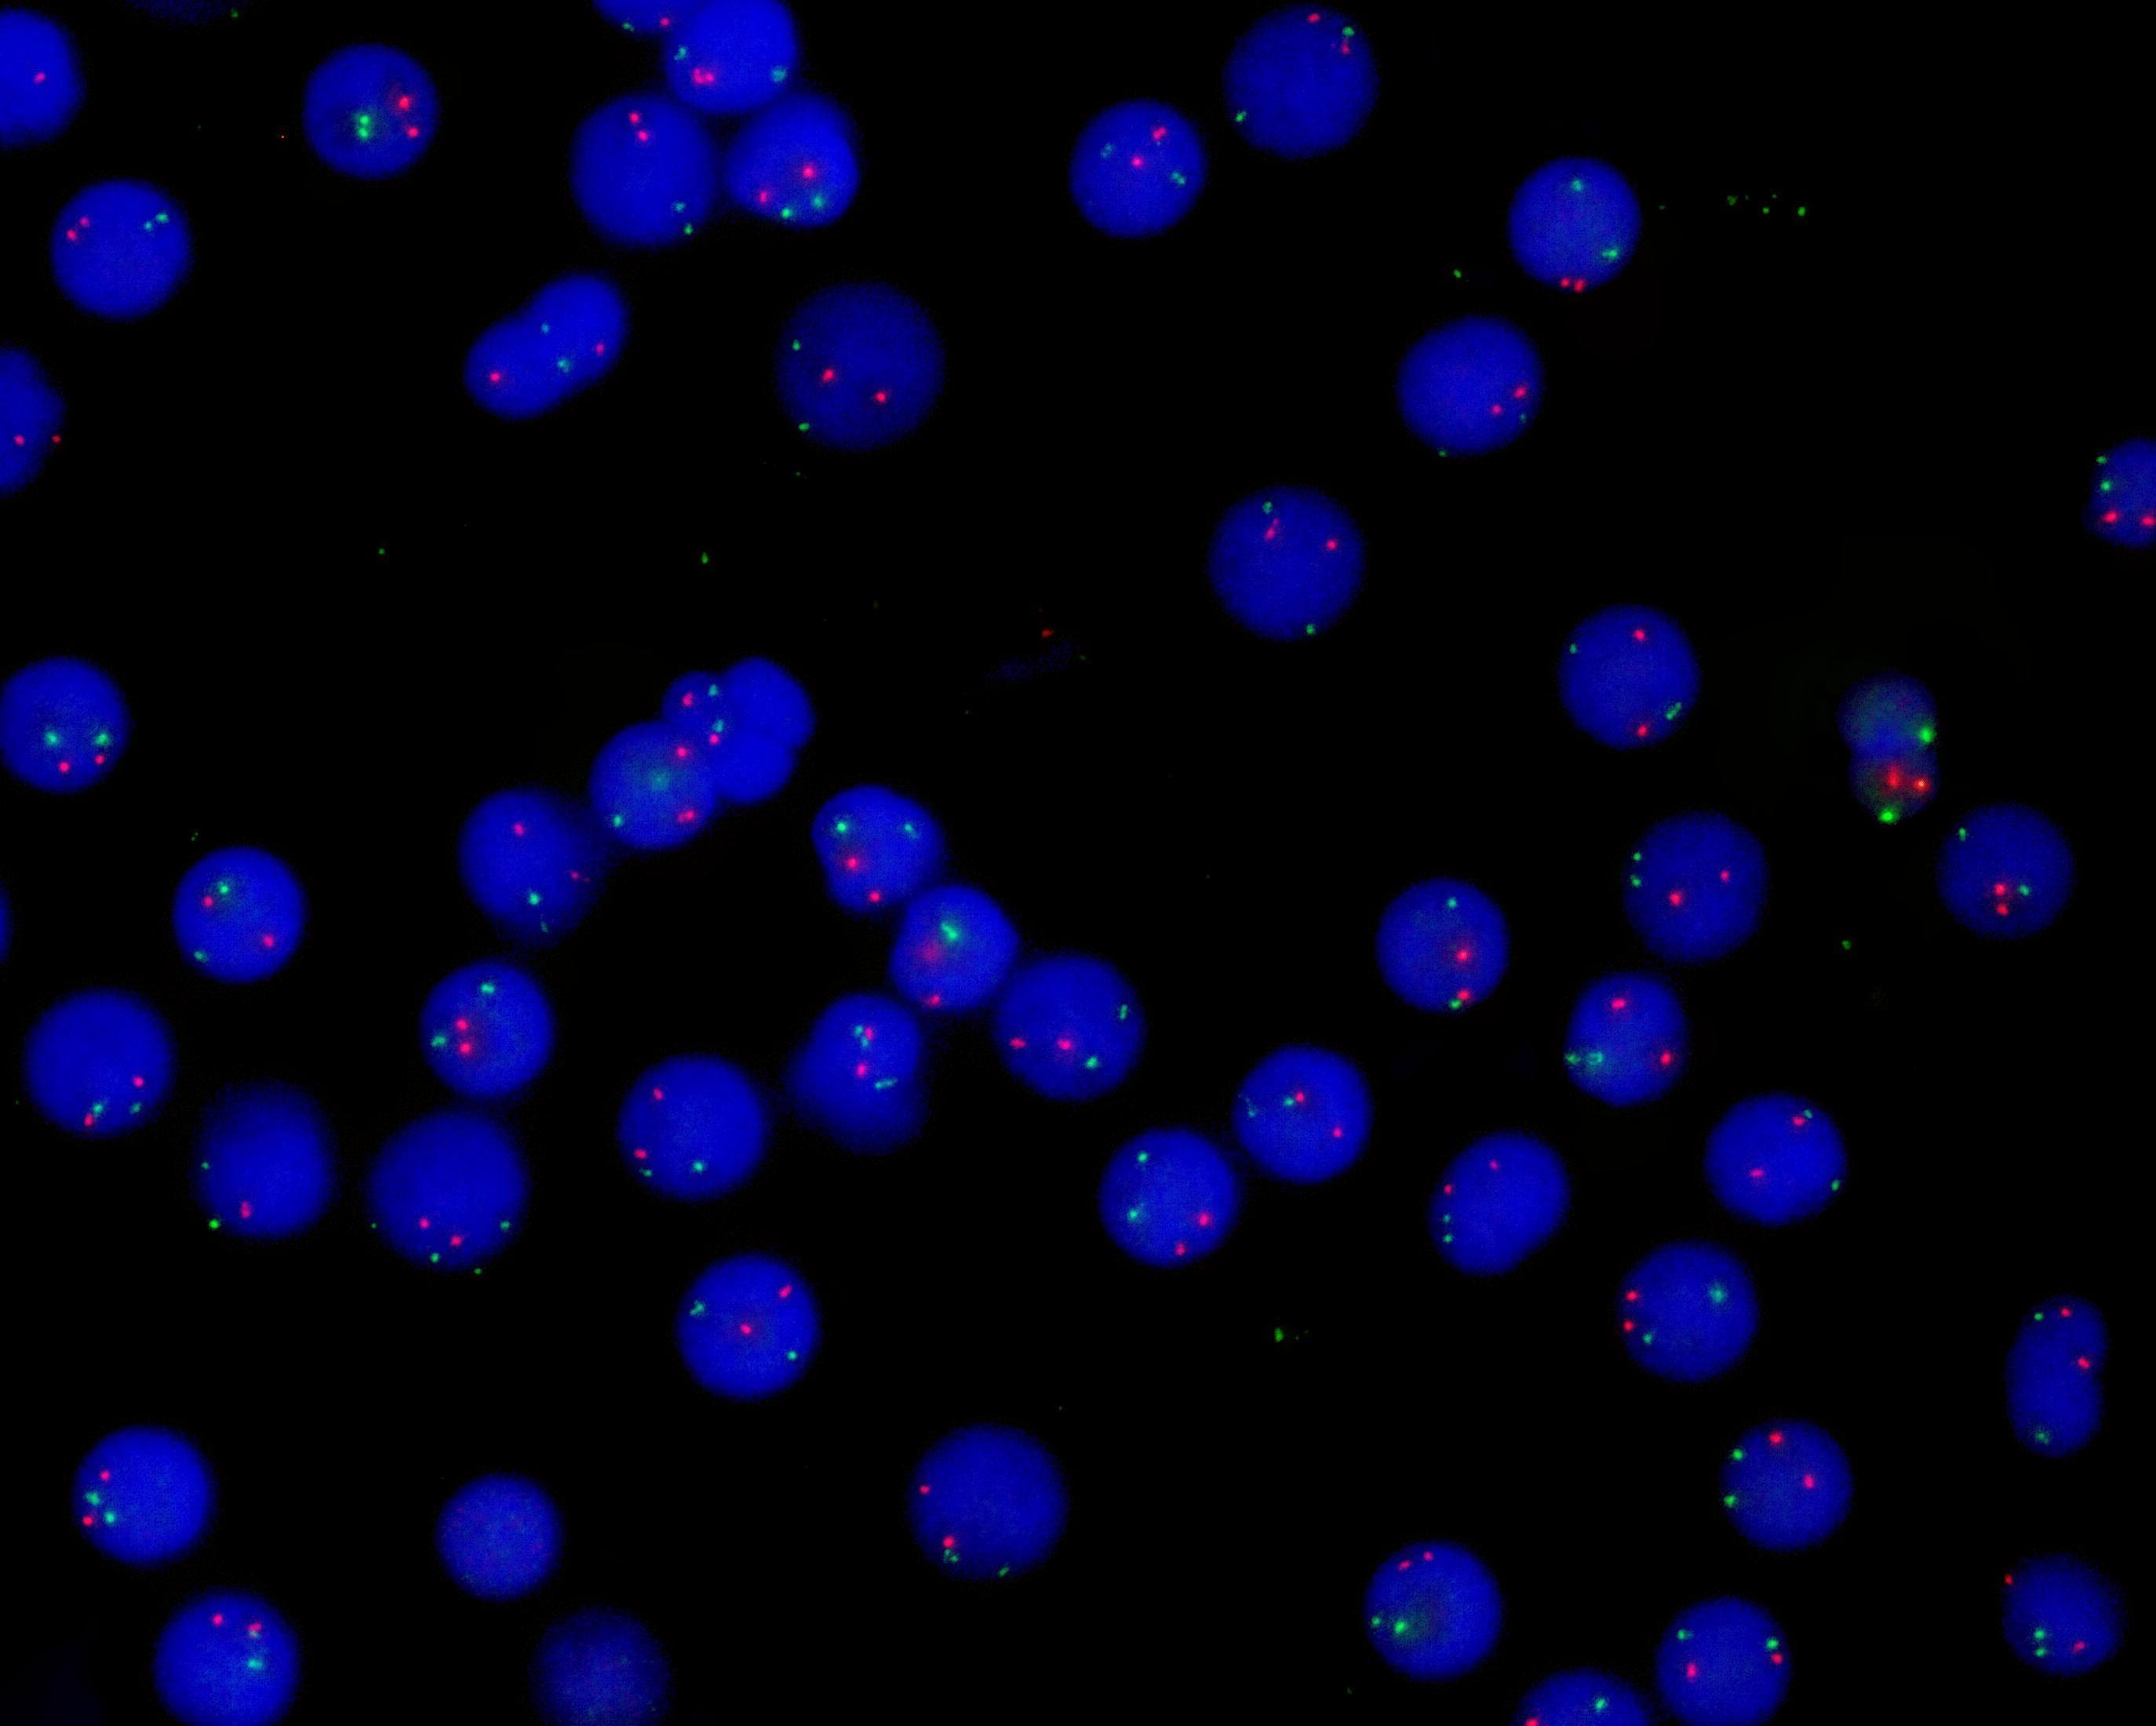

RB1/ATM dual color probe

RB1 gene (13q14.2) labeled as orange, with a length of 325 kb; ATM gene (11q22.3) labeled as green, with a length of 500 kb.